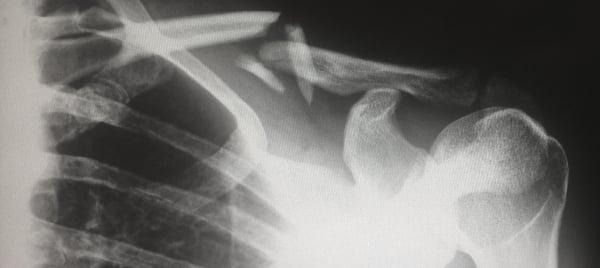

The first three stages of the Tour were fraught with crashes. You hate to see them, but also somehow can’t look away from when they occur. One of the most common bike injuries is a broken clavicle (i.e. collarbone). This has always struck me as rather peculiar, since cyclists hardly ever fall directly onto the collar bone. If the impact hits elsewhere, why is the collar bone so snappy?

The collar bone acts as a strut providing structural support by connecting the top of the sternum (i.e. breast bone) to the scapula (i.e. shoulder blade). When cyclists take a spill, it’s often the shoulder or an outstretched arm connected to the shoulder that takes the greatest impact, causing the collar bone to break. This actually “helps protect the arm by dispersing force transmitted through direct contact.”

Regrettably, a broken collarbone is just a part of cycling – one of the risks we accept when climbing into the cockpit. For its part, a collar bone heals relatively quickly and easily. Immobilize it. Ice it. For simple breaks, give it about eight weeks and you’re back in action. Yes, there are more severe breaks and complications are possible, but c’mon, glass half full and all that.

There is disappointingly little useful information online about how to prevent collar bone breakage while cycling. As such, I’m left to impart general riding safety knowledge to you, dear reader. These tips that have served me well and kept me reasonably intact over the years: know your limits, leave enough following distance, assume you're invisible to drivers, and have fun. Oh, and I suppose I should add one more: take care of your bones. Odds are, they’re the only ones you’ve got for the rest of your life, and they tend to work better in one piece.